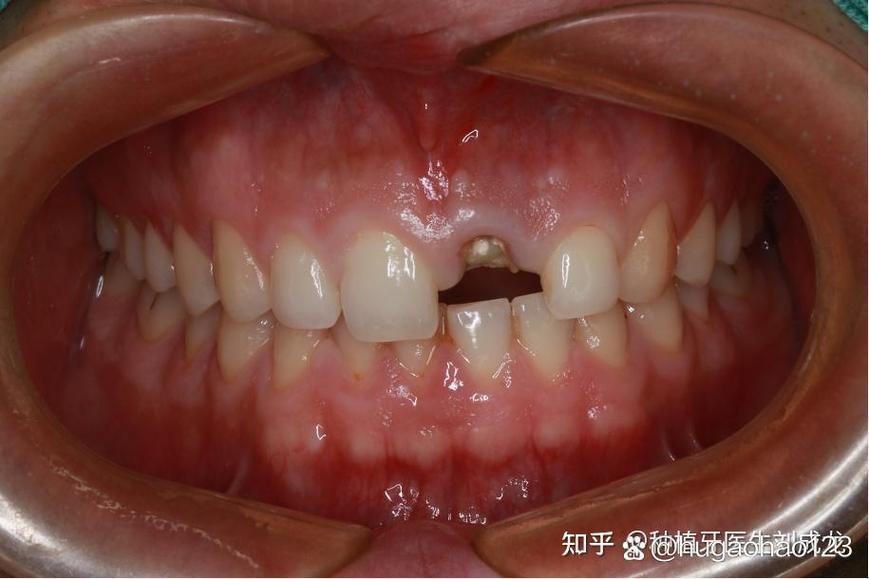

(图片来源网络,侵删)- 骨组织再生:拔牙后牙槽骨会逐渐吸收,若骨量不足,需先进行骨增量手术(如植骨、骨粉填充),等待骨结合完成。

(图片来源网络,侵删)- 术后24小时冰敷脸颊,避免剧烈运动。